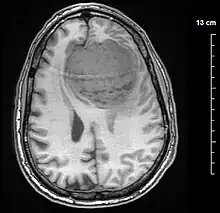

![]() | |

| An MRI of the brain, demonstrating the appearance of a meningioma | |

Diagnosis

Meningiomas are visualized readily with contrast CT, MRI with gadolinium,[23] and arteriography, all attributed to the fact that meningiomas are extra-axial and vascularized. CSF protein levels are usually found to be elevated when lumbar puncture is used to obtain spinal fluid. On T1-weighted contrast-enhanced MRI, they may show a typical dural tail sign absent in some rare forms of meningiomas.[18]